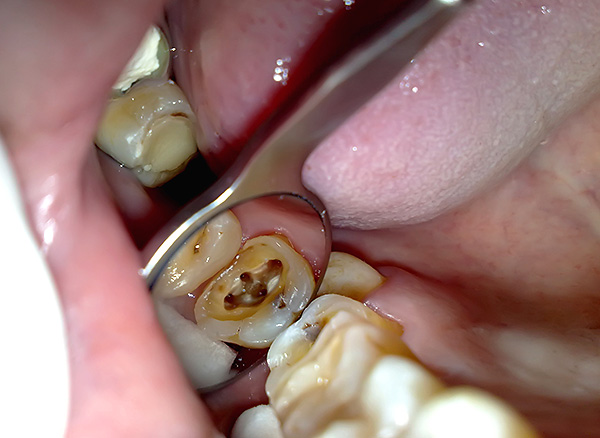

O médico não curou todos os canais do dente

Com o tratamento endodôntico, o médico precisa criar acesso a todos os canais radiculares do dente - para isso, você precisa encontrá-los todos e abrir a boca. Para pessoas diferentes nos dentes com o mesmo número de série, o número de canais pode variar e também pode haver um número diferente de ramificações.

Nota

A anatomia do sistema radicular do dente pode ser comparada a uma árvore. Nas raízes dos dentes, a polpa preenche canais especiais e, como regra, seu número corresponde ao número de raízes, mas muitas vezes existem canais adicionais.

Os canais radiculares têm uma parte estuarina (início) se comunicando com a coroa e uma parte apical (no segmento final da raiz), na qual há uma abertura anatômica - o ápice através do qual ocorre a comunicação com os tecidos circundantes das gengivas e osso da mandíbula.

Portanto, é inaceitável deixar pelo menos um canal com a infecção dentro. Deve-se entender que, nesse caso, o foco da inflamação não vai a lugar algum - ele se lembrará após o tratamento da pulpite, ou seja, o dente doerá. Pode não haver dores noturnas, mas será doloroso morder o dente por um longo tempo, e a patologia pode se transformar em uma forma crônica com a formação cistos na raiz do dente.